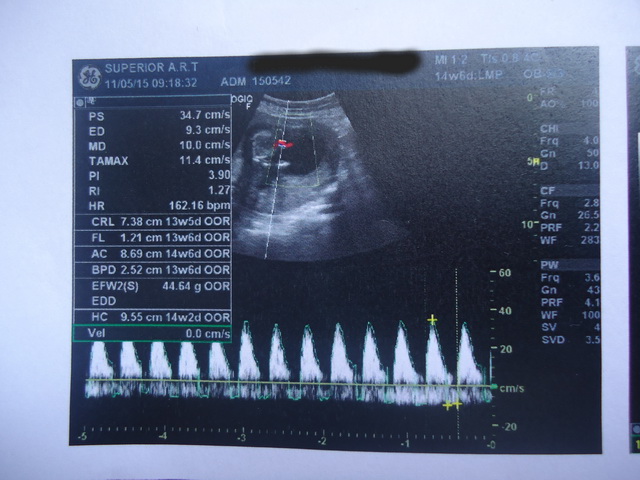

เราไป u/s มา อายุครรภ์ประมาณ 13-14 สัปดาห์ ตามรูปค่ะ

2. ปจด.ครั้งสุดท้ายวันที่ 27 ม.ค.58 อายุครรภ์นับจากประจำเดือนกับอายุครรภ์ในผลตราซาวด์ไม่ตรงกันเป็นไรมั้ยคะ

เรายึดอันไหน

3. ขนาดของน้องเป็นยังไงบ้างคะตามเกณฑ์มั้ย